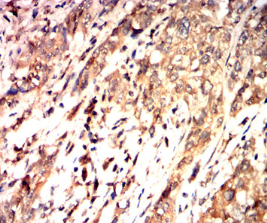

IHC    1/200 - 1/1000